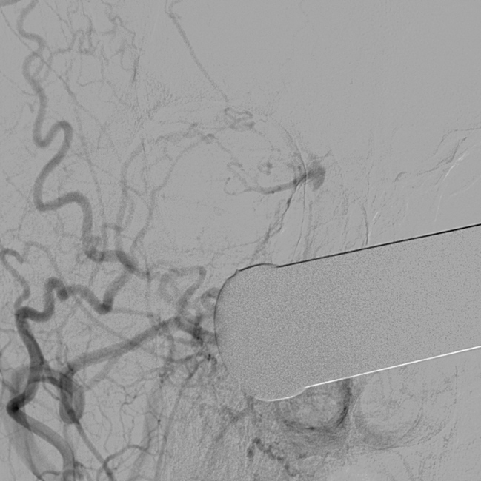

介入手术:(缺Fagarty /Merci/ Penumbra球囊导管、带膜支架)颈内动脉颅内外段置球囊保护,拔异物。

问题:1、颈内动脉破裂处理?2、取栓再通,如何防止血栓脱落?